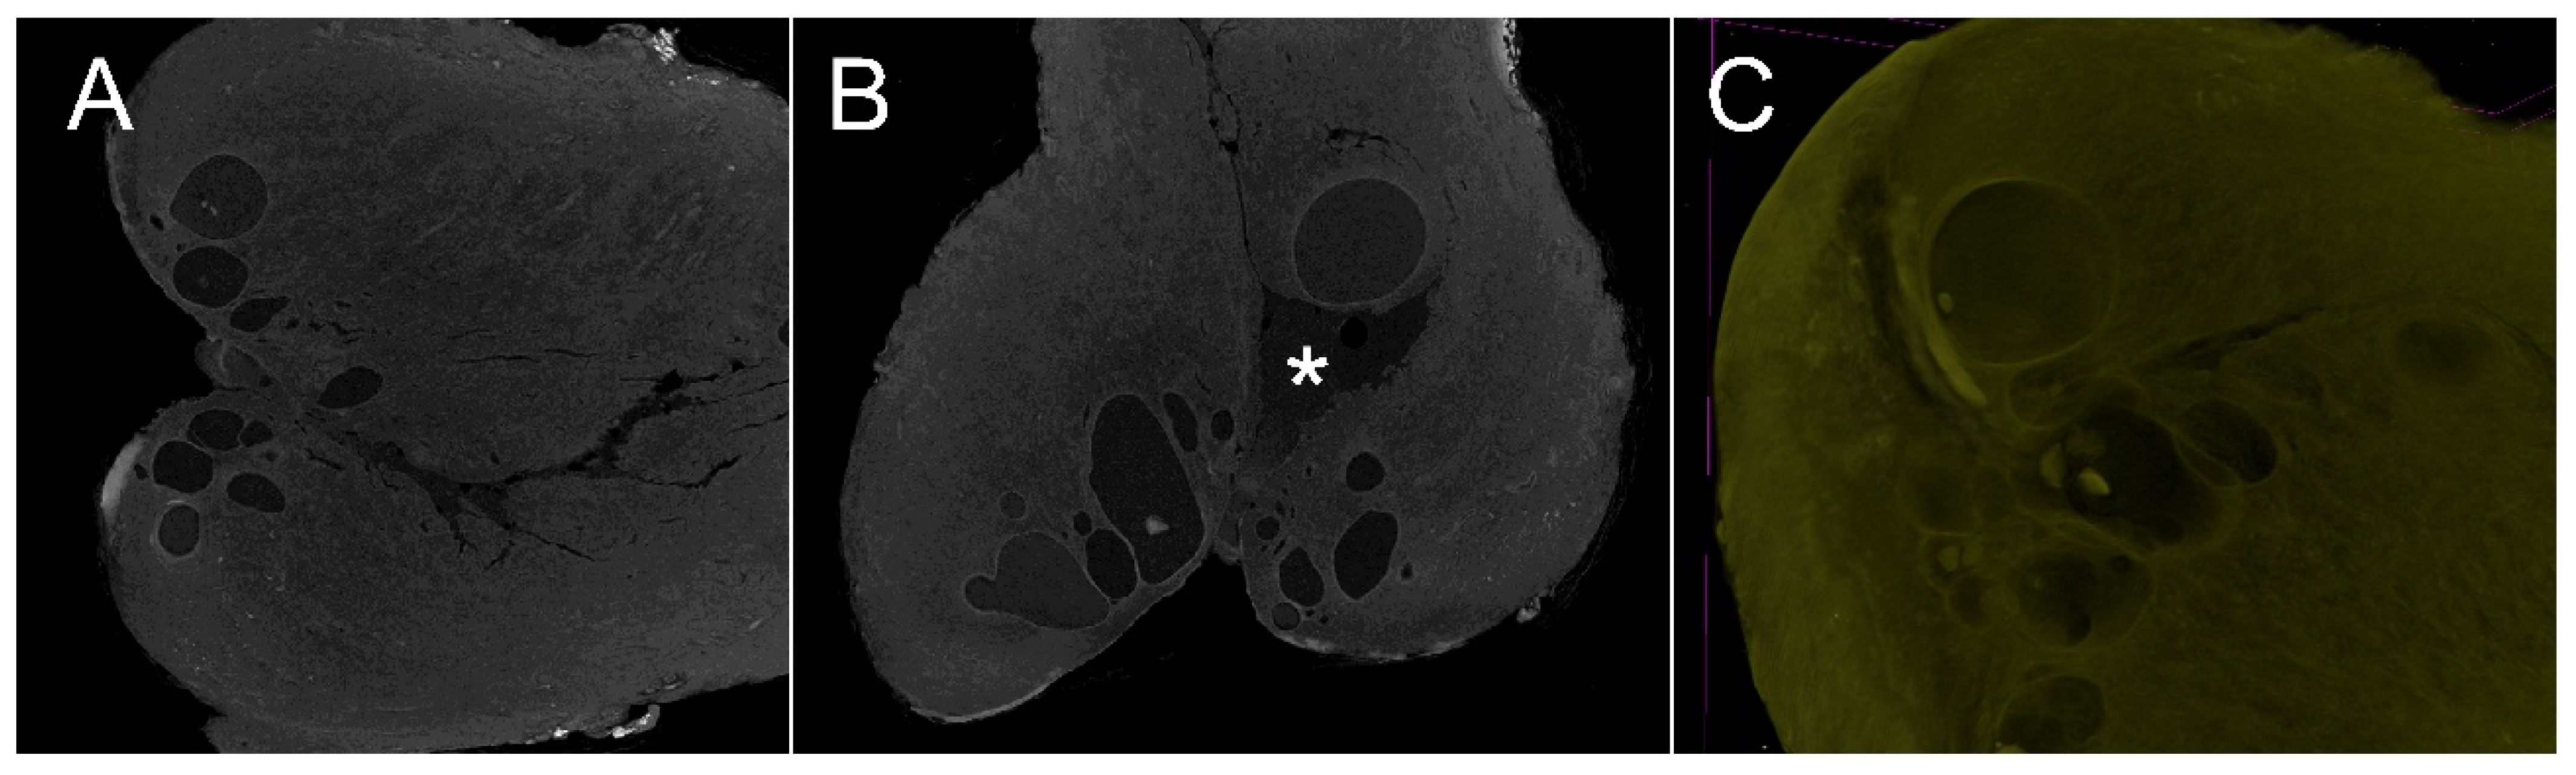

3.5. The Endocervical Anatomy

3.6. The Endocervical Canal Beyond the External os